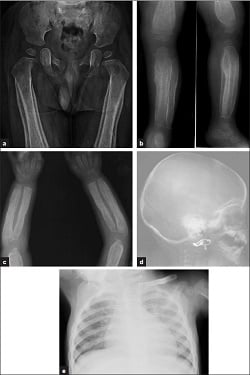

- Skeletal survey. A set of x-rays that look at the major bones in the body. It includes the skull, arms, legs, ribs, spine, pelvis, hands, and feet. These x-rays are looking for any problems with your child’s bones. The number of x-rays will depend on your child’s age. Your child will likely need a second part in 3 weeks. Central Scheduling staff can help you make this appointment.